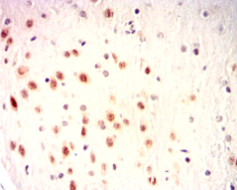

ISL1 Mouse Monoclonal antibody[1B1B8]

IHC    1/100 - 1/500